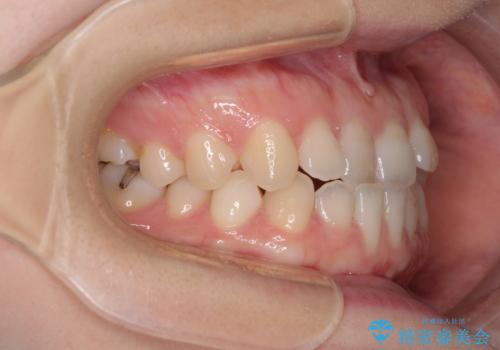

前歯のクロスバイト インビザラインによる矯正治療

- 前歯のクロスバイトとデコボコを気にして来院された患者様です。

骨格的に下顎前突傾向であるため、自己管理が煩わしくないようであれば、インビザラインによる矯正治療がお勧めとなります。

インビザラインを用い、下顎歯列を後方に移動させながら全市の被蓋を改善し、歯並びを整えていくこととしました。